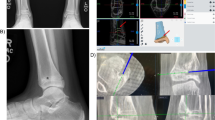

Doctors mostly work with two-dimensional X-ray images or two-dimensional images obtained from computed tomography (CT) or magnetic resonance (MR) scans to gain insight into pathologies. This requires excellent visualization skills from the surgeon. The recent emergence of three-dimensional renderings of CT, MR, plain radiography, and echo imagery has improved visualization of complex pathologies but lacks tactile qualities. 3D-printed objects can be used to study complex cases, to practice procedures, and to teach students and patients. [1].

Furthermore, some current surgical procedures are complex and require guidance to avoid damaging essential parts of the body, or to obtain an acceptable esthetic outcome [2]. In some cases, this guidance requires substantial amounts of ionizing radiation and can heavily increase surgical time [3]. Additionally, anatomical defects can require custom prosthetics to repair damage as accurately as possible [4].

The need for improved visualization and surgical outcomes has given rise to 3D-printed anatomical models, patient-specific guides, and 3D-printed prosthetics. The growing surgical applications of 3D printing have made it interesting to analyze the current implementation of this new technology.

3D-printed anatomical models see broad use in the surgical field. Our review suggests that, in orthopedics, their use has been shown to be beneficial, especially in complex hip replacements, where improved medical outcomes were reported unanimously. Also, studies of cranial (mostly orbital) fractures have reported improved results which have been credited to the use of anatomical models as guides prior to and during surgery, in order to understand the pathology better and to avoid pitfalls. These cranial anatomical models are often also used to shape the implant prior to surgery, resulting in an improved fit of the implant, improved medical outcome, and reduced surgical time. As with the anatomical models used for orthopedic and cranial purposes, our research suggests that spinal and maxillofacial models improve operation planning and clinical outcome, while reducing operation time. Furthermore, anatomical models can reduce the need for fluoroscopy during spinal surgery, reducing exposure to ionizing radiation.

Based on our findings, surgical guides seem to reduce operation room time and improve medical outcomes for spinal and cranial surgery. This is due to the simulation on models and the accurate translation of the preliminary surgery by means of guides. More than half of the selected studies reported reduced exposure to ionizing radiation (Additional file 1) due to the decreased need for fluoroscopy. In maxillofacial surgery, 3D-printed models and surgical guides are increasingly used for mandibular reconstructions and orthognathic surgery. The guides are used for the resection of both the mandibular part and the graft, as well as to reconstruct the missing part during oncological mandibular resections and reconstructions. According to the results of our research, spinal surgical guides translate the surgical planning accurately and make the outcomes less dependent on the surgeon’s experience. Similar results are seen with the use of guides during dental surgeries. Some authors question the systematic use of dental guides because of the associated higher costs, and suggest that guides be used only in complex cases. Finally, 3D-printed stereotactic fixtures can be used to guide implantation of deep brain stimulation implants with a substantial reduction of surgical time.

The accuracy of the guide or model and the accurate placement of the guide play important roles in the final clinical outcome or advantage provided by the model. The overlap between accuracy and clinical outcome is therefore unavoidable. The accuracy of guides can vary depending on the manufacturer providing the 3D-printed element and the time between the scan used for the production of the guide and the moment of surgery. Furthermore, surgical experience is needed to detect defective guides. Finally, the use of MRI or CT has an impact on the accuracy of the guide.